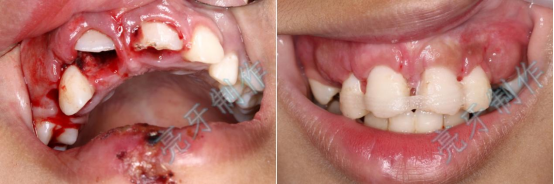

病例二:外伤导致上牙槽骨骨折,而且上下两颗门牙脱位;通过治疗,上下两颗门牙均恢复原来位置,而且和之前一样结实。

病例五:牙齿嵌入牙槽骨,牙龈撕裂,治疗后,恢复了自信和美丽的笑容。